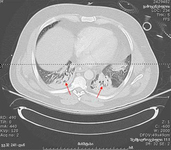

პაციენტის კომპიუტერული ტომოგრაფია, რომელსაც აქვს მარცხენა ქვედა წილის ალვეოლური ინფილტრაცია (ლურჯი ისარი), ორმხრივი პლევრალური ექსუდატი (ყვითელი ისრის წვეტები) და მარჯვენა ბაზილარული ატელექტაზი; ყურადღება მიაქციეთ ხაზს, რომელიც მიჯნავს ნაცრისფრის ორ ტონს, რომელთაგან ერთი წარმოადგენს ინფილტრაციას და მეორე სითხეს.

თანხმობა მიღებულია ლუისვილის უნივერსიტეტში, ლუისვილი, კენტუკი